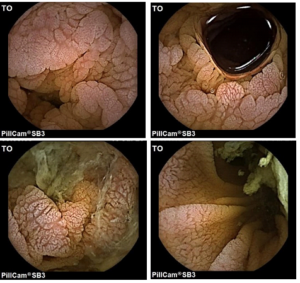

Doença celíaca

Hospital de São João (Porto)